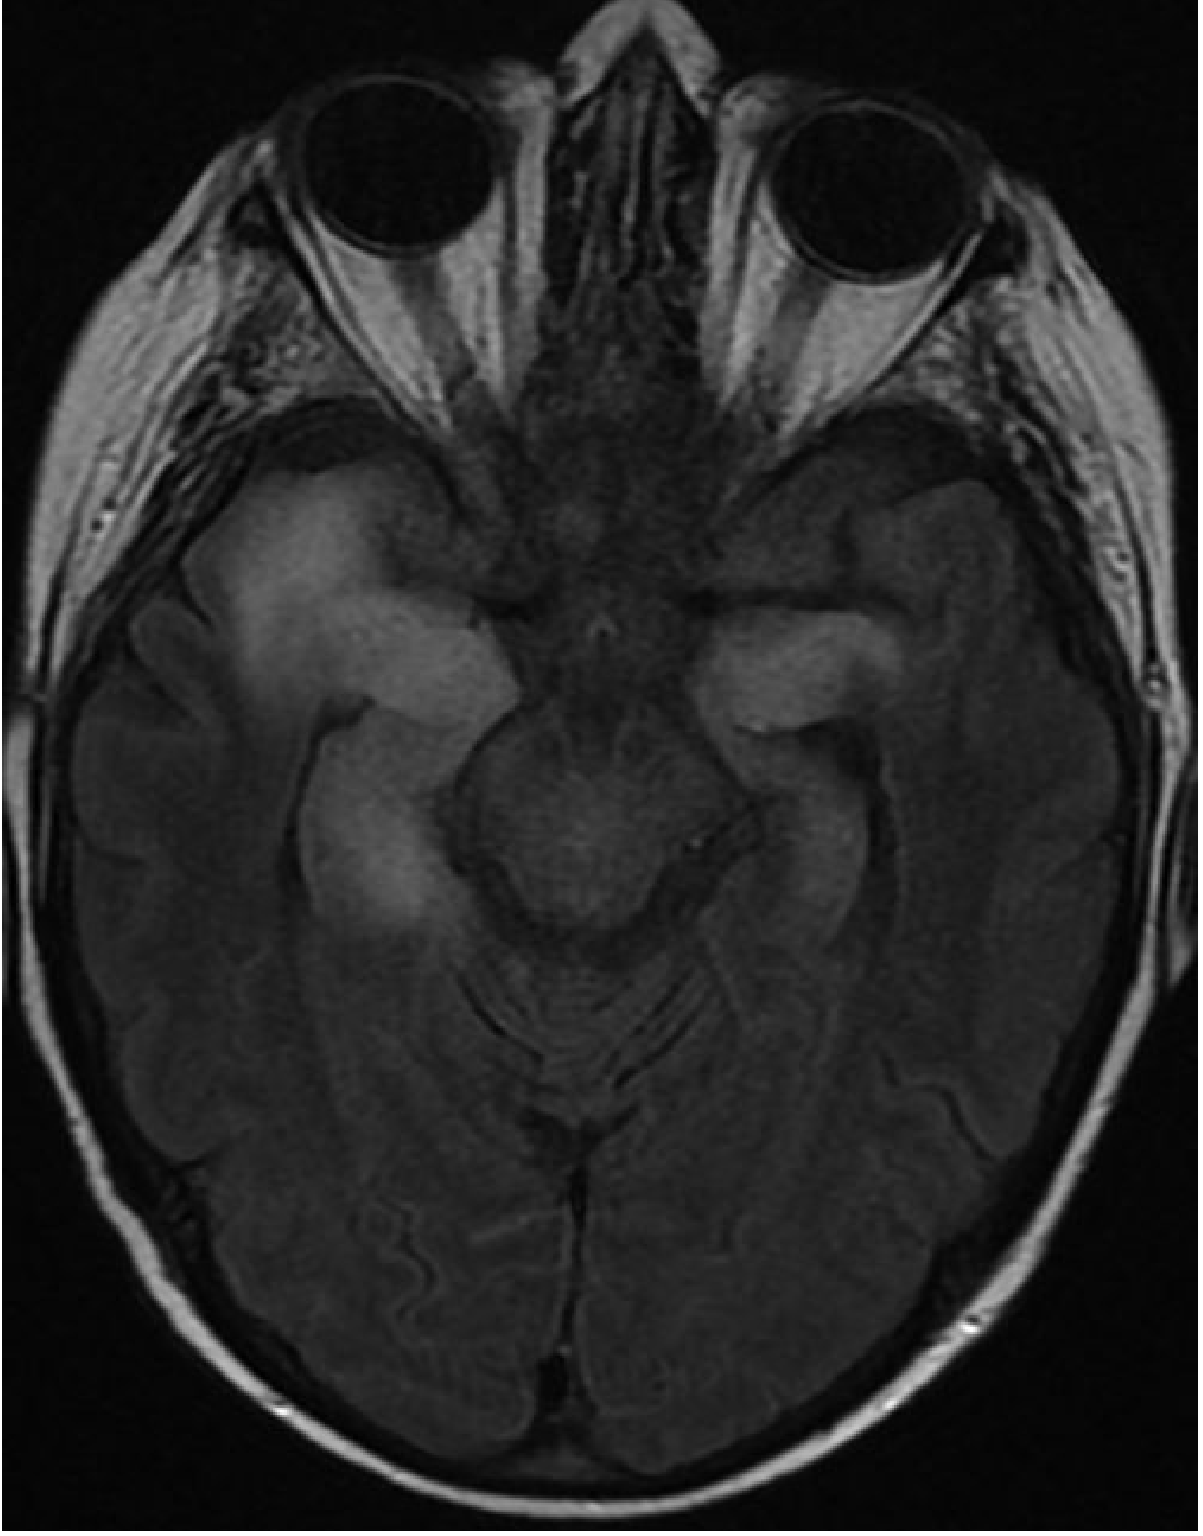

| FLAIR / T2 | High signal + cortical swelling in anteromedial temporal lobe, insula, cingulate β earliest and most sensitive; abnormal within 2 days |

Abnormalities start unilaterally but frequently spread to the contralateral temporal lobe. Bilateral involvement on MRI is a poor prognostic sign.

| MRI hallmark | Temporal T2/FLAIR swelling | Diffuse WM T2, atrophy | Meningeal enhancement; infarcts | DWI cortical ribboning | Basilar enhancement; hydrocephalus |